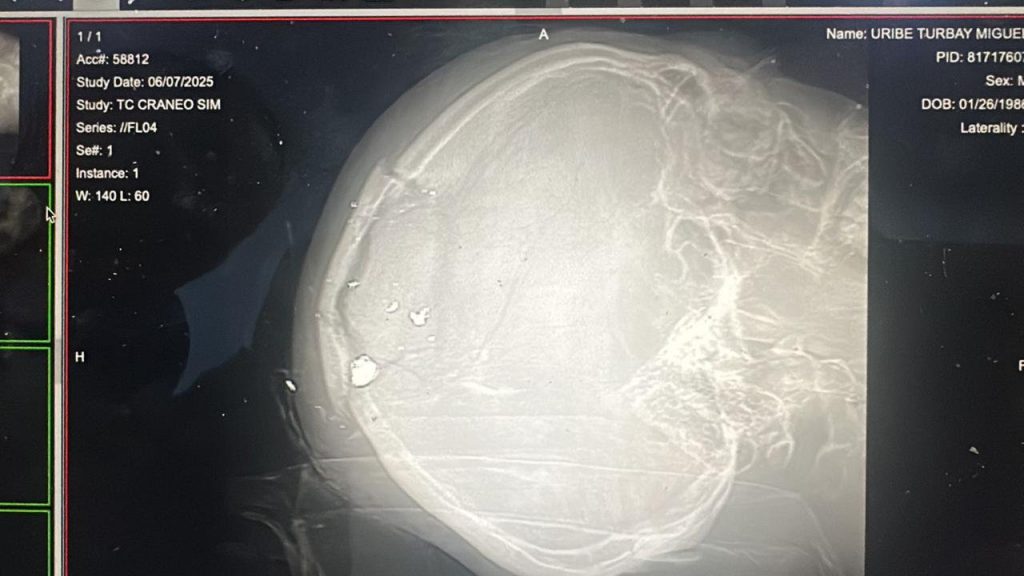

La radiografía de cráneo de Miguel Uribe Turbay. Información preliminar señala que el precandidato presidencial tiene el proyectil alojado en la parte superior del cráneo.